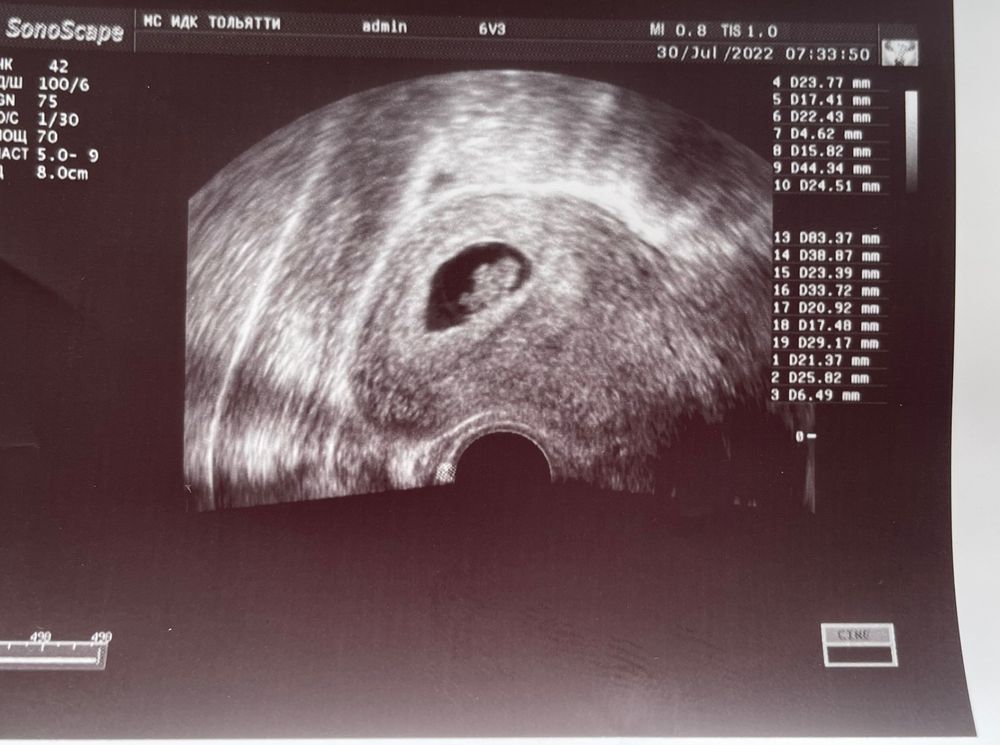

Прикрепляю фото моего Узи!!! Вторая беременность! Что вы думаете на счёт этого.

Трансвагинально, 8 недель

Трансвагинально, 8 недель